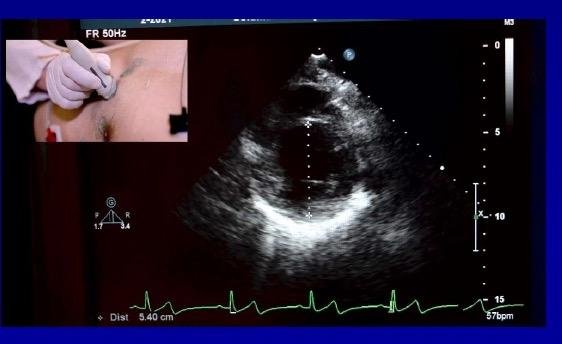

- For selecting and measuring from the appropriate end-diastolic from the file “Apical4chVolunteer”, you can check the file “Cardiac_demo_patient_long_axis” to check which one the physician selected. Similarily, for selecting from the short-axis views, you can use the file “Cardiac_demo_patient_short_axis” also in attached files. Both images are shown below:

- Develop a routine on Matlab that you can use to manually measure the diameter of the left-ventricular cavity on the images after loading. Make sure to indicate the points on the image and properly calibrate your method. For calibration, you can use the scale next to the image (to shown during the introductory presentation). Each tick mark on the scale is in cm.